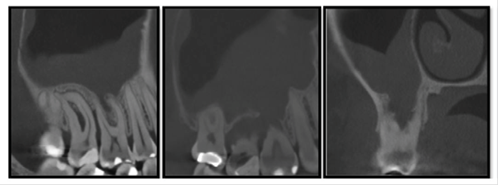

A 33-year-old man reported an episode of bleeding in the mouth and extravasation of fluid through the nose during liquid ingestion. The bleeding occurred in the upper right first molar region over one year, and there was extravasation of blood and serous fluid through the nose associated with pain and pressure on the same side of the face, when the patient was yawning. The medical condition did not show any comorbidity. In the intraoral exam, a 7mm periodontal pocket was detected. A gingival recession was also observed around the UFM and a Valsalva test was negative. The panoramic x-ray showed vertical bone loss in the super right first and second molar (URFSM) region. There was a bilateral alveolar ex-tension of maxillary sinus with opacification on the right maxillary sinus only (figure 2). We prescribed a CBCT exam, which showed severe furcation in-jury, external root reabsorption and vertical bone loss around cortical floor, and a thickening of the sinus mucosa around the URFSM. There was a rupture in the floor of the cortical sinus (figure 3). The diagnostic hypothesis was OMS related to periodontal disease or maxillary sinus tumor of the maxillary sinus floor. The extraction of the URFSM was done with curettage of the soft tissue associated with dental roots. In the surgical procedure, a 1cm diameter oroantral communication was observed, treated with intra alveolar fibrin sponge covered with a vestibular flap of oral mucosa (figure 4). The microscopic analysis showed no signs of malignancy and chronic inflammatory cell infiltrate compatible with inflammatory periodontal disease (figure 5). The final diagnosis was odontogenic maxillary sinusitis related to periodontal disease. A corticosteroid nasal spray was prescribed, and three months after the surgical procedure no clinical signs or symptoms were observed. A new panoramic x-ray six months after the surgical procedure showed normal radiopacity of the right maxillary sinus (figure 6).